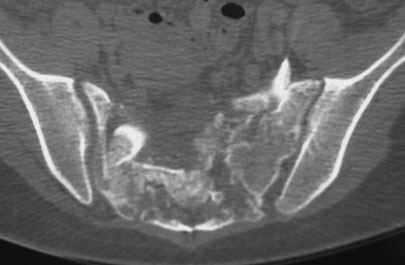

Травма 21.августа 2005г. На девочку в лесу упала береза. Доставлена в ближайшую ЦРБ. При поступлении установлен диагноз: Травматический шок 2-3 ст. Тупая травма живота. Забрюшинная гематома. Перелом костей таза с нарушением целостности тазового кольца. Перелом лонной и седалищной костей справа. Перелом поперечных отростков L3 - L5. Разрыв КПС справа. При поступлении выполнена диагностическая лапароскопия — выявлена обширная забрюшинная гематома. Было наложено скелетное вытяжение за бугристости обеих б/берцовых костей, больная уложена в гамак. Через неделю скелетное вытяжение демонтировано, гамак снят. Девочка уложена в положение «лягушки». Контрольные рентгенограммы через 4 недели после травмы. Заподозрен перелом дужки L5. Больная 26 сентября 2005 г. переведена в областную больницу в отделение детской ортопедии. При поступлении в локальном статусе: пальпация и перкуссия остистых и поперечных отростков L4-5 болезненная. Пальпация костей таза б/болезненная. С-м натяжения слабо положителен. Осевая нагрузка положительная. Движения в т/б суставах ограничены, болезненны. C-м прилипшей пятки отрицательный. C-м Ларрея и Варнейля отрицательный. Периферическая гемодинамика не нарушена.Неврологический статус: вторичная двусторонняя радикулопатия L5-S1. 29 сентября произведена компьютерная томография позвоночника и таза.

Судя по томограммам, радикулопатия может быть из-за компресии "конского хвоста" смещенным крестцовым позвонком, это хорошо видно на втором слева снимке. Если этот сегмент будет нестабилен и будет сохраняться неврологическая симптоматика, придется оперировать. Если неврологическая симптоматика уйдет и перелом стабилизируется, то можно обойтись без операции.